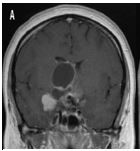

O uso de ressonância magnética de crânio para conferir a presencia de massa tumoral é mais fidedigna. Nas sequencias T1WI achamos sinal variável devido ao conteúdo do cisto, muitas vezes hiperintensidade devido ao material proteico, enquanto o componente tumoral sólido pode ter aspecto heterogêneo ou isointenso. No T2WI os cistos são tipicamente hiperintensos com focos hipointensos devido a calcificações. O T2 * / GRE / SWI encontramos um sinal “preto” que floresce secundário à calcificação ou sangue. São tumores que captam contraste na parte solida, mesmo sendo de origem benigna.

Volumosa lesão expansiva selar supraselar, heterogênea, solido cística. Ressonância Magnética, T1, corte coronal contrastada, volumoso componente cístico ocupando o III ventrículo, cístico com sinal hiperintenso, alto conteúdo proteico (A), sinal hipointenso em T1 coronal, na porção solida, com realce de contraste (B), sequência T2 mostrando áreas hipointensas sugestivas de calcificação (C), TC de crânio demonstrando as calcificações intratumoral..